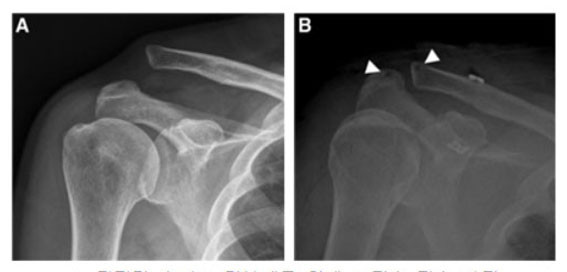

Á¤Çü¿Ü°ú ¼ö¼ú °ü·Ã SCOPUS±Þ ±¹Á¦ÇмúÁöÀÎ ¡®Arthroscopic technique¡¯¿¡ ¹ßÇ¥ÇÑ À̹ø ³í¹®Àº ¡®Arthroscopic Acromioclavicular Fixation With Suture Tape Augmentation After Coracoclavicular Fixation With Dog Bone Button : Surgical Technique¡¯¶ó´Â Á¦¸ñÀ¸·Î ¾î±ú ÀÎ´ë ¼Õ»óÀÇ °üÀý°æ Ä¡·á¹ý¿¡ °üÇÑ ³í¹®ÀÌ´Ù.

| | ¡è¡è ¡ã°üÀý°æ ¼ú±â·Î °ßºÀ¼â°ñ ÀÎ´ë °íÁ¤¼ú ÀüÈÄ »çÁø <»çÁøÁ¦°ø=õ¾È¡¤¾Æ»êÃæ¹«º´¿ø> | ¨Ï ¿Â¾ç½Å¹® | | À¯À缺 ±³¼ö´Â À̹ø ¿¬±¸¿¡¼ ¾î±ú °ßºÀ ¼â°ñ ÀÎ´ë ¼Õ»ó Ä¡·á ½Ã ±âÁ¸ ¼ö¼ú¹ý¿¡¼ ³ªÅ¸³ª´Â ¼öÁ÷ ¾ÈÁ¤¼ºÀÇ Á¦ÇÑÁ¡À» ±Øº¹ÇϰíÀÚ °üÀý°æ ¼ö¼ú ±â¹ýÀ» °³¹ßÇÏ¿©, °á°úÀûÀ¸·Î ¼öÁ÷ ¾ÈÁ¤¼º°ú ¼öÆò ¾ÈÁ¤¼ºÀ» ¸ðµÎ ȹµæÇÏ´Â µî À¯ÀǹÌÇÑ ¿¬±¸ ¼º°ú¸¦ ³»¾ú´Ù.